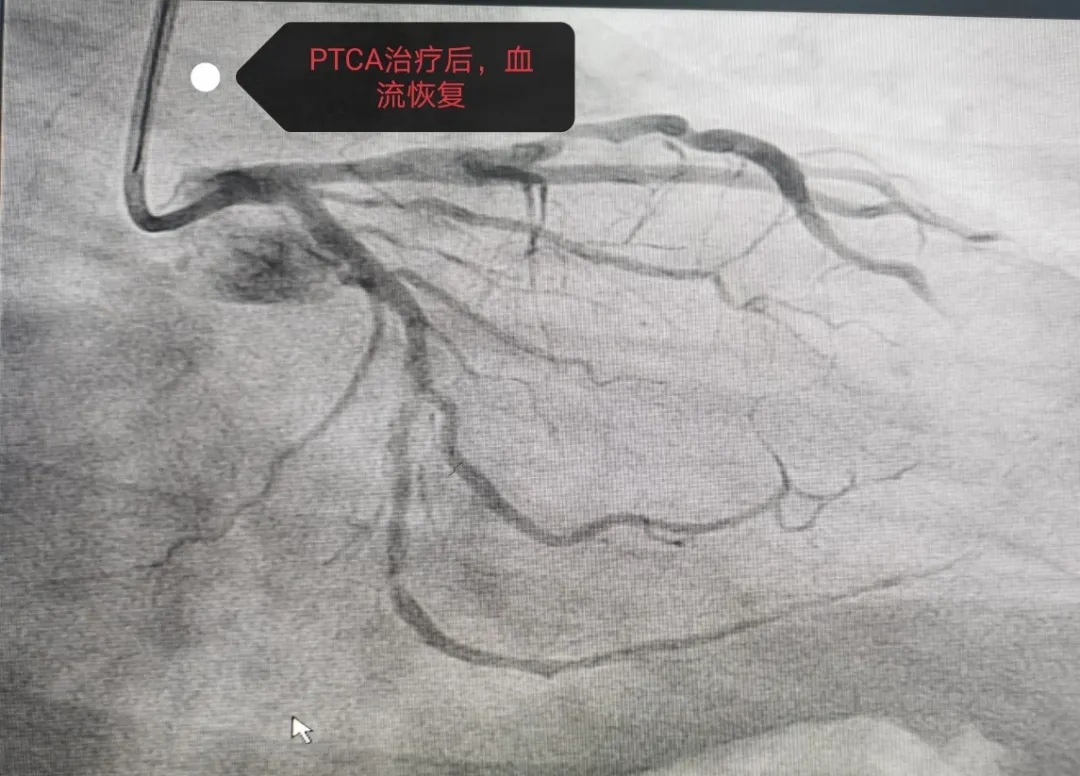

7月19日,前来医院体检的马某在检查冠状动脉造影时,显示左冠右冠分别有不同程度狭窄,冠狭窄50%左右,左回旋支全闭塞。院方立马与家属谈话同意治疗,给予NS导丝很难通过血管,又给予Fielder XT通过,判断出血管钙化严重,放支架不是最好的效果,便实施了PTCA球囊扩张治疗。经过介入团队2个半小时的努力,最终使患者受益,手术当下达到了最好的效果。患者亲属多有心脏搭桥手术,自身支架植入手术后无特殊症状,只是偶尔牙痛放射至心前区不适,本次手术后感觉轻松了很多。

患者术后血流恢复情况